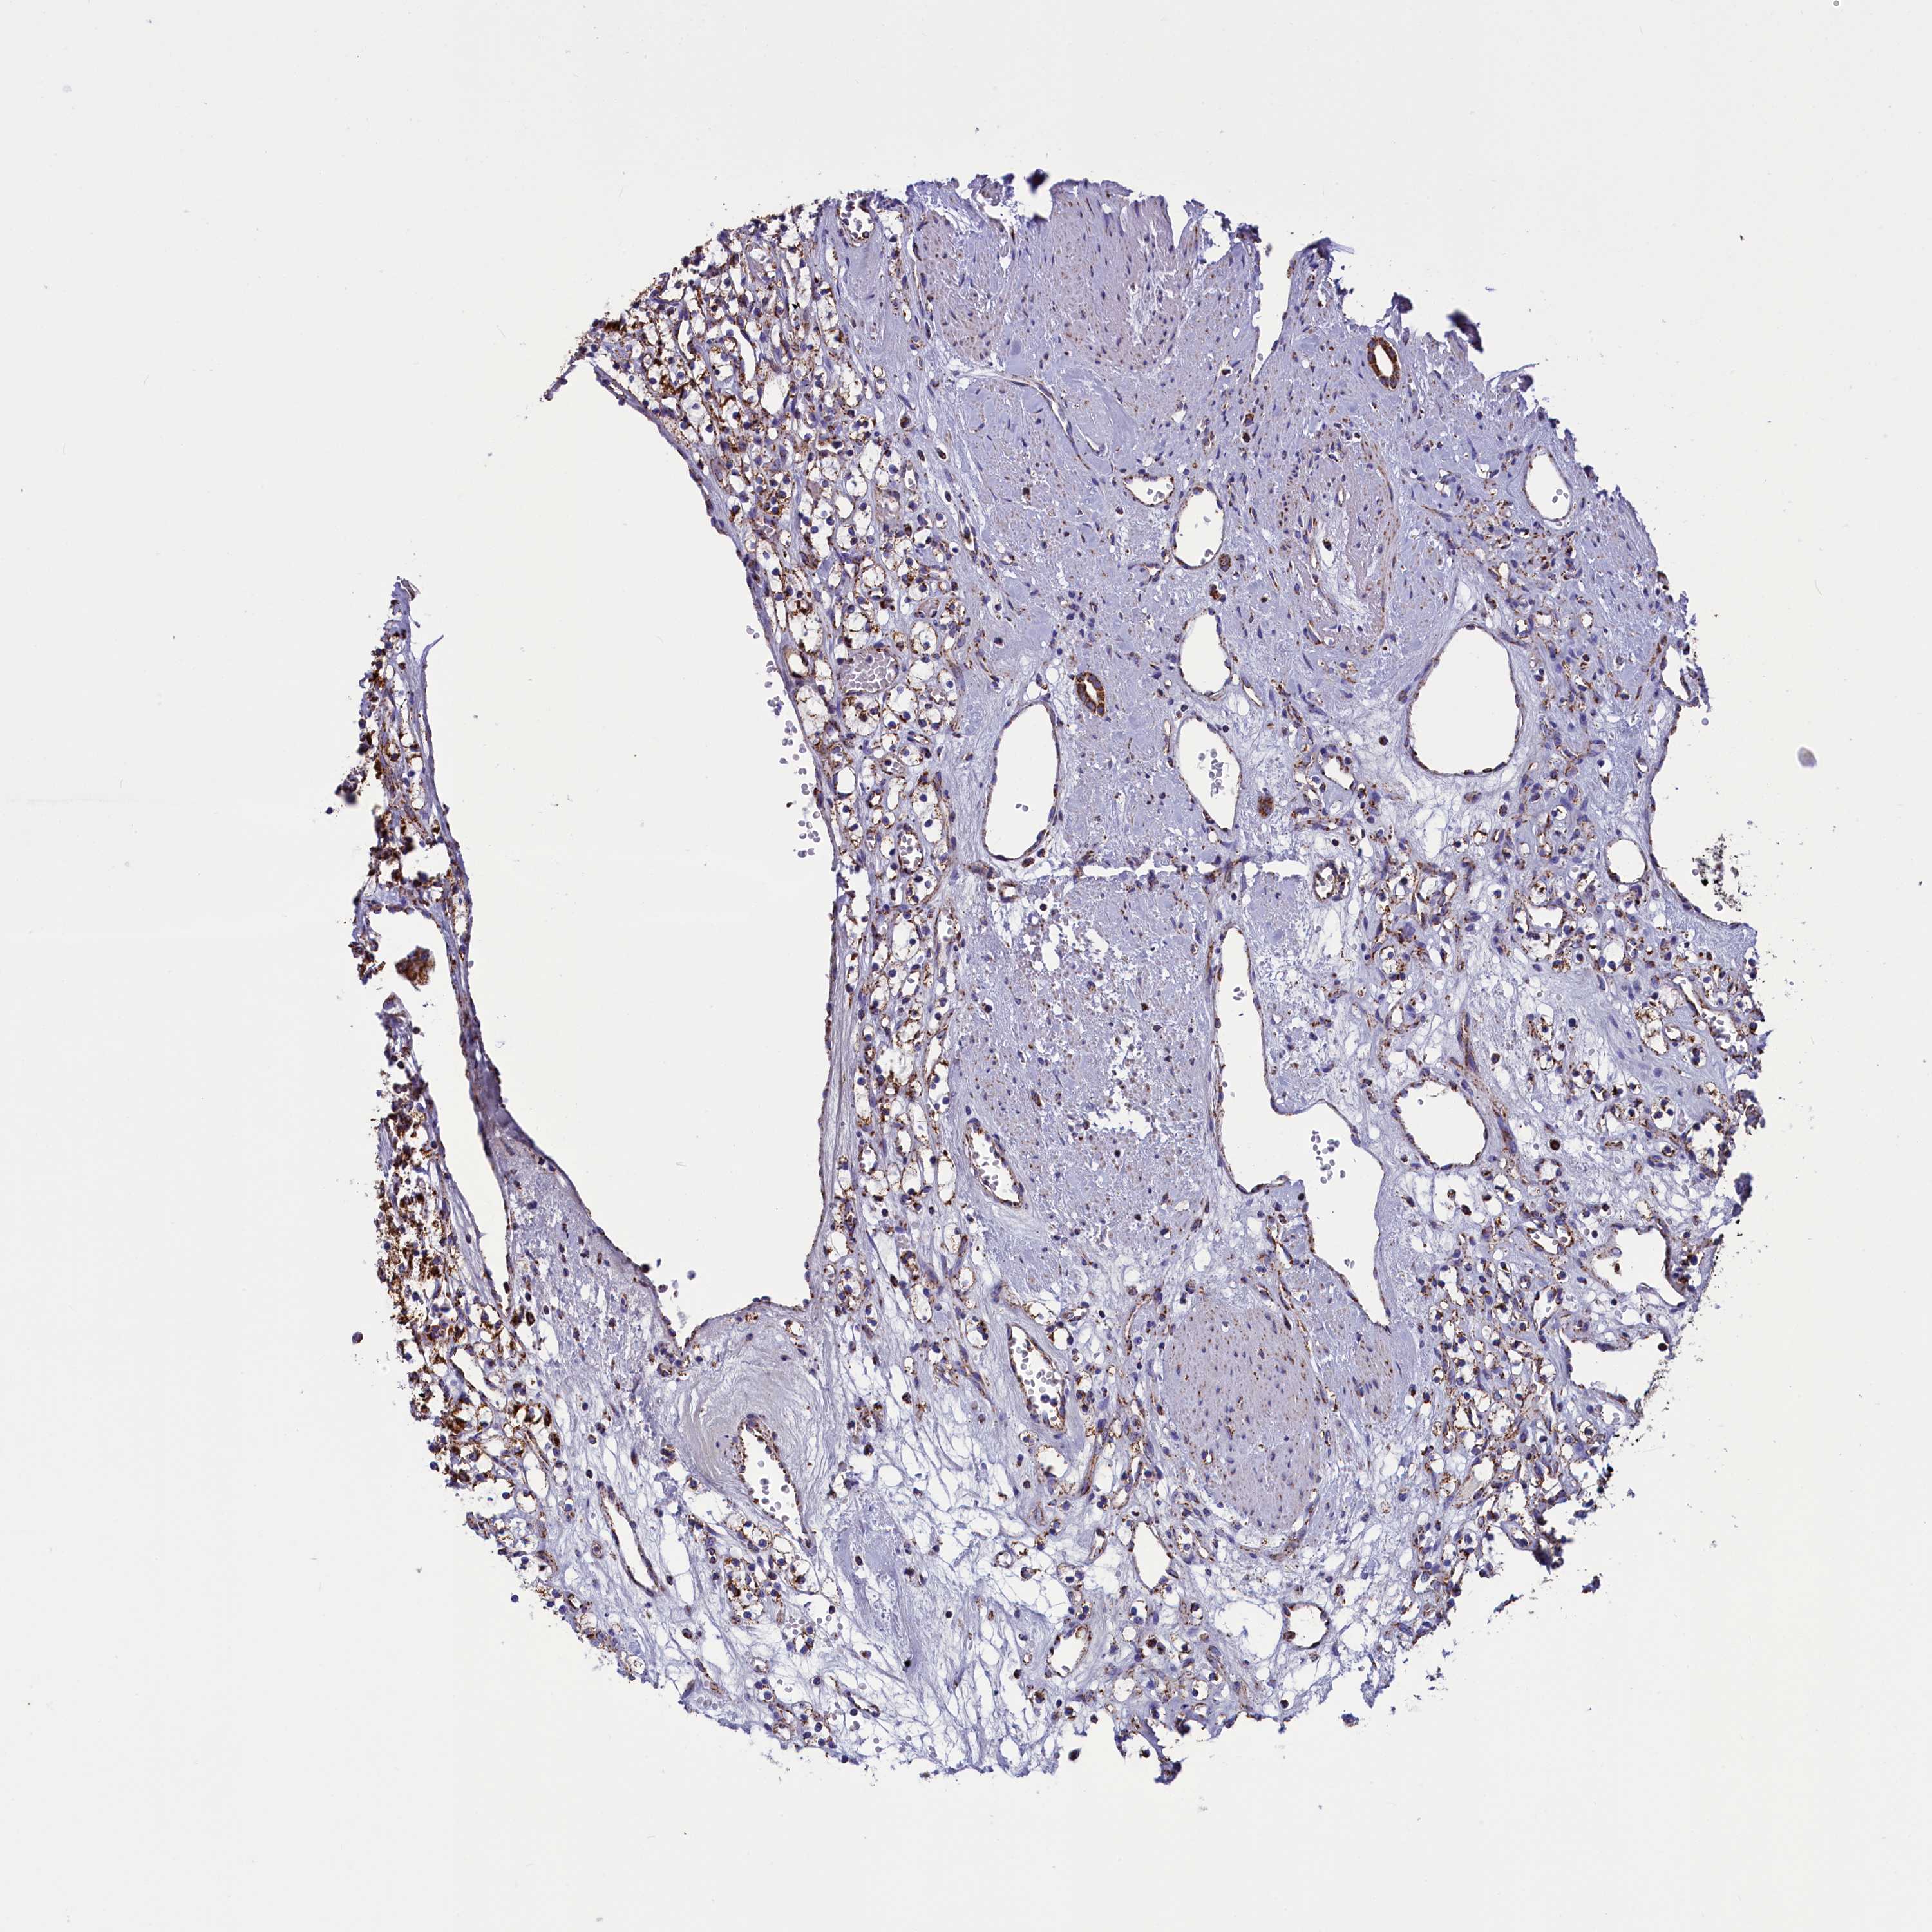

KIDNEY RENAL CLEAR CELL CARCINOMA (VALIDATION) - Interactive survival scatter ploti

The Survival Scatter plot shows the clinical status (i.e. dead or alive) for all individuals in the patient cohort, based on the same data that underlies the corresponding Kaplan-Meier plots. Patients that are alive at last time for follow-up are shown in blue and patients who have died during the study are shown in red.

The x-axis shows the expression levels (FPKM) of the investigated gene in the tumor tissue at the time of diagnosis. The y-axis shows the follow-up time after diagnosis (years). Both axes are complimented with kernel density curves demonstrating the data density over the axes. The top density plot shows the expression levels (FPKM) distribution among dead (red) and alive patients (blue). The right density plot shows the data density of the survived years of dead patients with high and low expression levels respectively, stratified using the cutoff indicated by the vertical dashed line through the Survival Scatter plot. This cutoff is automatically defined based on the FPKM cutoff that minimizes the p-score. The cutoff can be changed by dragging the vertical line or by entering a cutoff value in the square labeled "Current cut-off".

Under the Survival Scatter plot the p-score landscape (black curve; left axis) is shown together with dead median separation (red curve; right axis). Dead median separation is the difference in median mRNA expression between patients who have died with high and low expression, respectively. It is calculated as follows: median FPKM expression of dead patients with high expression - median FPKM expression of dead patients with low expression. This is intended to aid the user in visually exploring custom cutoffs and the associated p-scores and dead median separation.

Individual patient data is displayed and can be filtered by clicking on one or more of the category buttons on the top of the page. Categories describing expression level and patient information include: high, low, alive, dead, female, male and tumor stages. The scale of the x-axis can be toggled between linear and log-scale by clicking on the "x log" button. Mouse-over function shows TCGA ID, patient information and mRNA expression (FPKM) for each patient.

& Survival analysisi

Kaplan-Meier plots summarize results from analysis of correlation between mRNA expression level and patient survival. Patients were divided based on level of expression into one of the two groups "low" (under cut off) or "high" (over cut off). X-axis shows time for survival (years) and y-axis shows the probability of survival, where 1.0 corresponds to 100 percent.

SLC39A3 is not prognostic in Kidney Renal Clear Cell Carcinoma (validation)

Best expression cut offi

Based on the FPKM value of each gene, patients were classified into two groups and association between prognosis (survival) and gene expression (FPKM) was examined. The best expression cut-off refers the FPKM value that yields maximal difference with regard to survival between the two groups at the lowest log-rank P-value. Best expression cut-off was selected based on survival analysis .

When clicking on this number, the vertical dashed line indicating cut-off, the interactive survival plot, and the Kaplan-Meier curve will be adjusted to show results based on the best expression cut-off.

: 22.48

TCGA RNA samplesi

RNA-seq data is reported as average FPKM (number Fragments Per Kilobase of exon per Million reads), generated by the The Cancer Genome Atlas (TCGA) .

Normal distribution across the dataset is visualized with box plots, shown as median and 25th and 75th percentiles. Points are displayed as outliers if they are above or below 1.5 times the interquartile range. FPKM values of the individual samples are presented next to the box plot.

Average pTPM 18.4

Number of samples 100